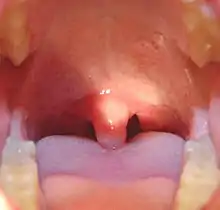

![]() Mouth of a child showing the uvula and swollen tonsils | |

The uvula (pl.: uvulas or uvulae), also known as the palatine uvula, is a conic projection from the back edge of the middle of the soft palate, composed of connective tissue containing a number of racemose glands, and some muscular fibers.[1][2] It also contains many serous glands, which produce thin saliva.[3] It is only found in humans.[4]